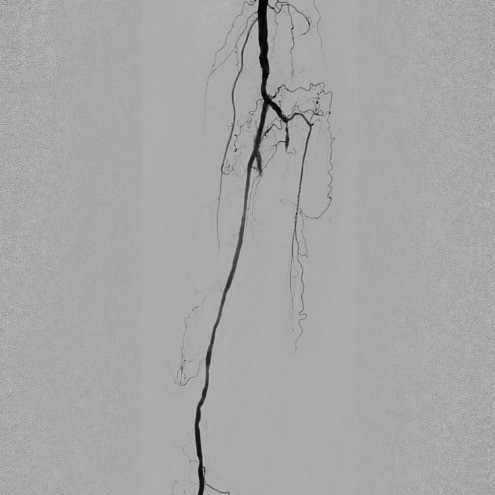

ABI检查(踝肱指数)提示左侧下肢动脉严重狭窄或闭塞。超声提示双侧股总动脉、股浅动脉等多部位动脉内中膜增厚,可见多发斑块;左侧胫腓干动脉、腓动脉及双侧胫前动脉管腔闭塞,左侧胫后动脉及双侧足背动脉依赖侧支血管代偿(流速异常)。

术前CTA进一步证实:左侧胫腓干动脉、腓动脉闭塞,双侧胫前动脉闭塞,病变范围广且涉及多支重要下肢动脉。

术前影像

造影显示左侧胫腓干动脉闭塞,胫后动脉通过侧支循环显影,左侧腓动脉及胫前动脉全程闭塞。